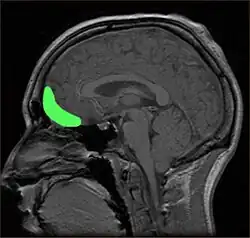

Within the brain, there is some support for the role of the orbitofrontal cortex (OFC) in producing self-conscious emotions, such as shame (Beer, et al., 2003; Leary, 2007; Sturm, Ascher, Miller, & Levenson, 2008). People with damage to the OFC have shown impairments in both the ability to appropriately express self-conscious emotions, such as shame, and in their social behaviour (Beer et al.). In Beer and colleagues' (2003) study, participants with OFC damage were more likely to overshare intimate information on a disclosure task, for example, telling about cheating on their partner, whereas other participants gave more guarded answers, such as being embarrassed when they did not understand a punchline. Those with OFC damage were also less likely to recognise self-conscious emotions on a recognition test than participants without any damage, although there was no difference between the groups in recognising other emotions (Beer et al.). This inability to correctly detect others' emotional responses suggests people with OFC damage may be missing important signals that their behaviour is inappropriate, such as others' embarrassment (Beer et al.). However, since others do not have to be real or physically present for a person to experience shame or the other self-conscious emotions, this suggests damage impairs the ability to correctly infer others' reactions to behaviour (Beer et al.).